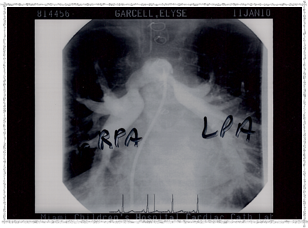

Second Catheterization — Dr. Danyal Khan

In 2010, Elyse underwent her second catheterization procedure, overseen by Dr. Danyal Khan at Miami Children's Hospital. The procedure focused on her pulmonary arteries, and these images show the before and after.

2010 - Left Pulmonary Artery After

Left Pulmonary Artery — After

2010 - Pulmonary Artery Ballooned

Pulmonary Artery ballooned